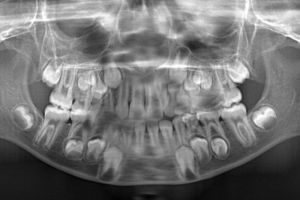

Yirmi yaş dişleri olarakta bilinen üçüncü azı dişleri sıklıkla kemik içerisinde gömülü kalabilir ya da yanlış bir pozisyonda sürebilir. Bu durumda cerrahi yöntemlerle lokal anestezi altında çekilmeleri gerekmektedir. Bazen gömülü kalmış köpek dişlerine de aynı tip cerrahi işlemler uygulanabilir.